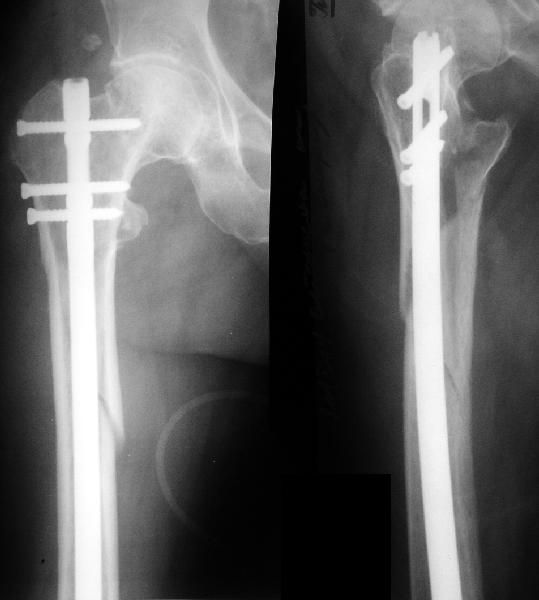

Alexander Chelnokov 21 Январь 2004, 09:05

Вчера оперировали - винты удалены через 1 прокол. Затем выполнили закрытый интрамедуллярный остеосинтез без расверливания бесканальным гвоздем 13 мм (реконструкционного для нее не нашлось). Гвоздь заперт статически - в проксимальный отломок 3 винта 6 мм, в дистальный - 1.

Учитывая варус сросшейся шейки, постарался вальгизировать проксимальный отломок, насколько гвоздь позволил. Результат в приложении. Картина перелома видна лучше, чем на начальных снимках.

Интересно, что линия перелома не выходила на отверстия от винтов, а была кзади. Комментарии?

The screws were removed through a stab wound. Then a closed insertion of an unreamed solid nail 13 mm was performed and the nail statically locked - 3 screws 6 mm in the proximal fragment and 1 in the distal.

Considering varus of the healed neck i tried to get some valgus to the proximal fragment as the nail allowed. The result attached. The fracture pattern can be seen better than in the initial films.

Any comments?